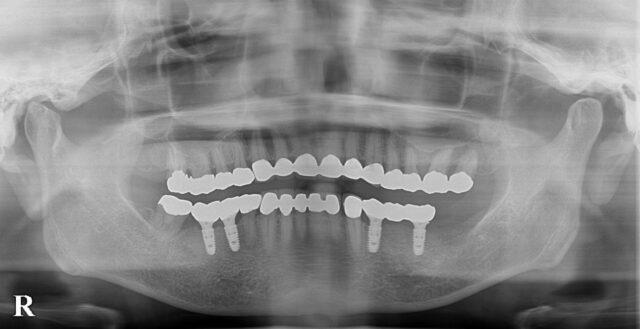

| 通院時の年齢 | 60代 |

|---|---|

| 性別 | 女性 |

| 通院回数 | 3ヶ月 |

| 通院目的 | 入れ歯が嫌なのでインプラントにしたい |

| 処置内容 | 右下65 左下46にインプラント |

| 費用 | 約170万円 |

| 備考 | 昔治療済の歯をそのままに入れ歯の部位のみ治療希望され、十分満足された。 |